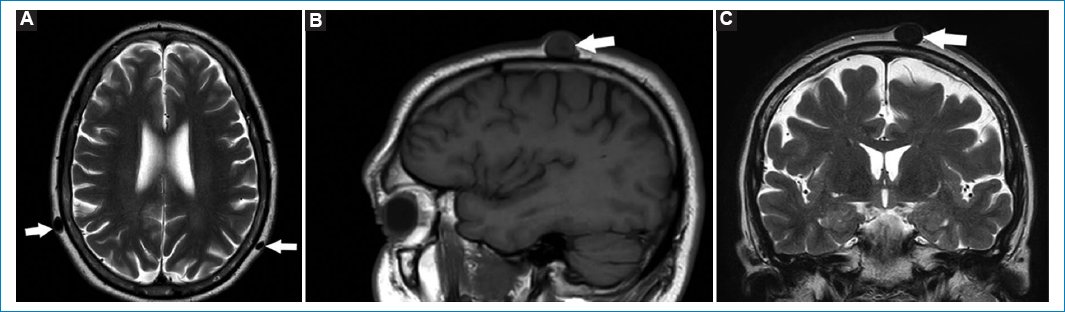

Los lipomas constituyen uno de los tumores benignos más frecuentes. De morfología redondeada y bordes bien definidos, se los aprecia hiperintensos tanto en secuencias ponderadas en T1 como en T2, por su rico contenido en lípidos. Las secuencias con supresión grasa son útiles para valorar la reducción de señal del lipoma (Fig. 14)34.

Figura 14. (A-C) Lipoma del cuero cabelludo, a nivel frontal izquierdo (flechas). Cortes: axial T1 (A), T2 (B) y sagital T1 (C). Se observa como una elevación con señal hiperintensa en su interior, por contenido rico en lípidos.

Los quistes sebáceos son formaciones quísticas bien delimitadas localizadas en la dermis. Si su contenido es rico en lípidos se aprecian hiperintensos en T1 y T2; en cambio, si el contenido es rico en queratina o pelo, puede valorarse como hipointensos/isointensos en T1 e hiperintensos en T2 (Fig. 15)34.

Figura 15. (A-C) Quistes sebáceos con contenido rico en queratina. Cortes: axial T1 (A), sagital T1 (B) y coronal T2 (C). Se muestran distintos pacientes en los que se observan (flechas) formaciones ovoides en el tejido celular subcutáneo, menores a un centímetro, con límites netos, que abomban la dermis. Son isointensos/hipointensos en T1 y T2.